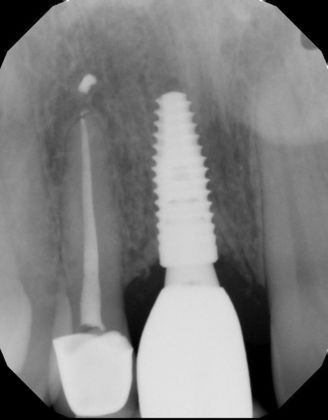

Replacing a missing upper central with an implant and a screw retained implant crown